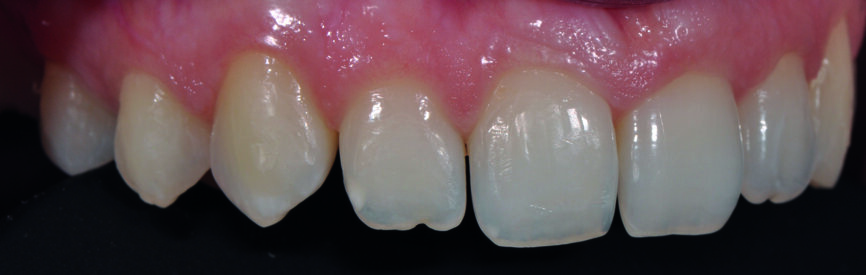

Fig. 1a : Sourire après la fermeture orthodontique.

Fig. 1b : Gros plan du sourire après la fermeture orthodontique. Il faut noter l’aspect jaunâtre des canines, les grandes embrasures des incisives et la ligne gingivale égalisée.